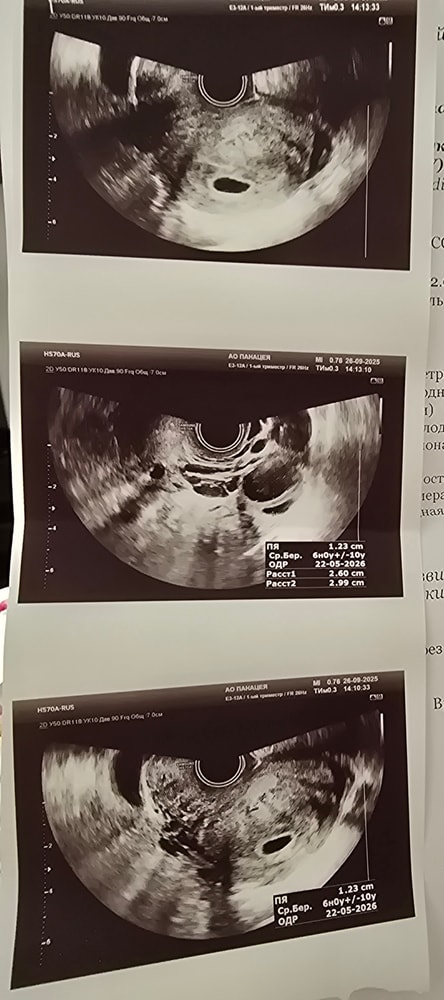

Срок 6 нед и 3 дня

Сегодня была на узи, плодное яйцо 12 мм(соответствует 6 нед.беременности)

Но желточный мешок и эмбрион не визуализируется

Последнее хгч 15 сентября 2500

До это 11 сентября 1100

Рекомендовано через неделю повторное узи, записана 1 октября на узи в другую клинику